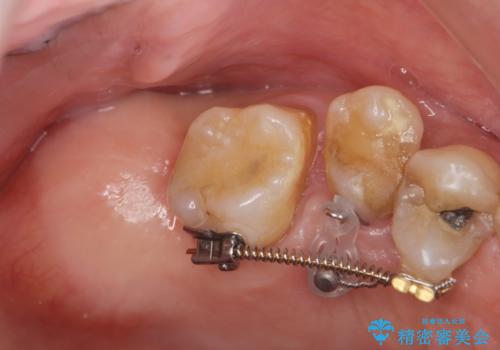

検査の結果、強い歯ぎしりによる歯の周囲の骨の吸収が認められたため歯槽骨の再生・歯周ポケットの除去・力に対抗する連結補綴・補綴前処置としての小矯正を計画します。

今回連結補綴を行うにあたり、歯周病の問題を解決するために再生療法・歯周ポケット除去手術を、またより歯の神経を保存し力に対抗できる環境を整えるために小矯正を行い精度の高いメタルボンドクラウンを製作することができました。